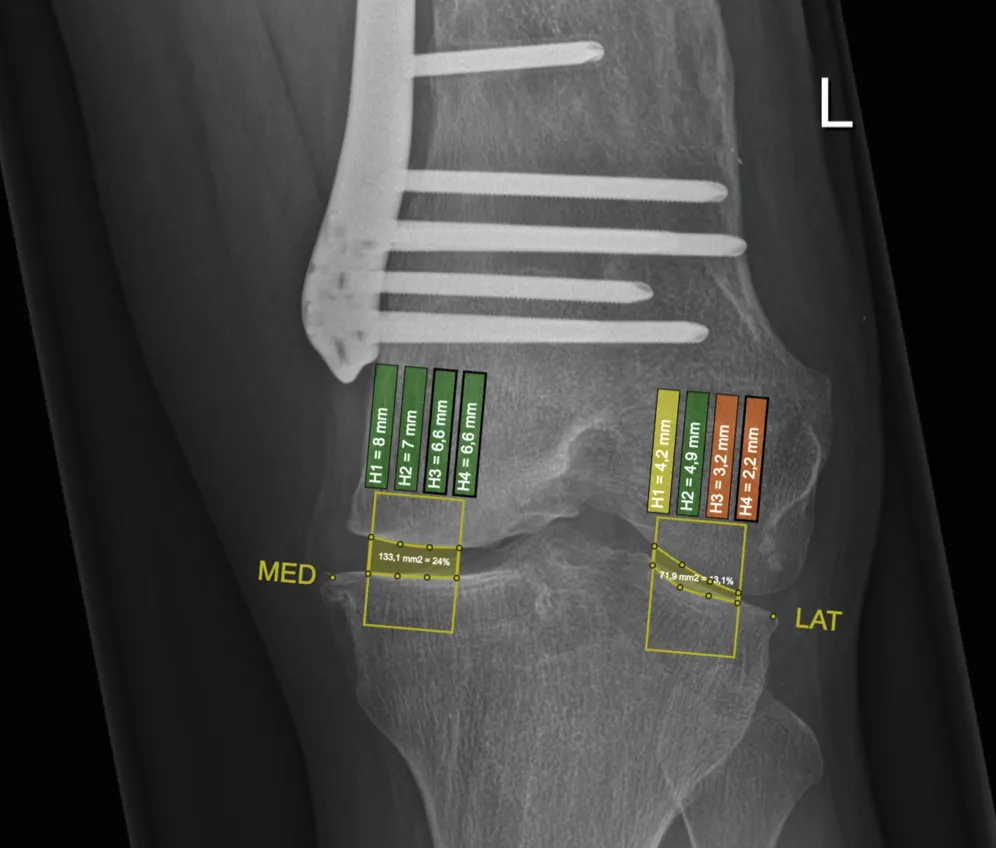

Developed an interactive clinical visualization system at ImageBiopsy Lab for analyzing osteoarthritis progression in knee joints. The platform integrated machine-learning models for automated landmark detection and quantitative measurement extraction from radiographic images, enabling structured visualization of joint-space narrowing and anatomical changes over time. The system translated computational imaging models into an accessible web-based analytical interface for research and clinical evaluation. The project formed the basis of my Bachelor’s thesis under the supervision of Prof. Eduard Gröller.